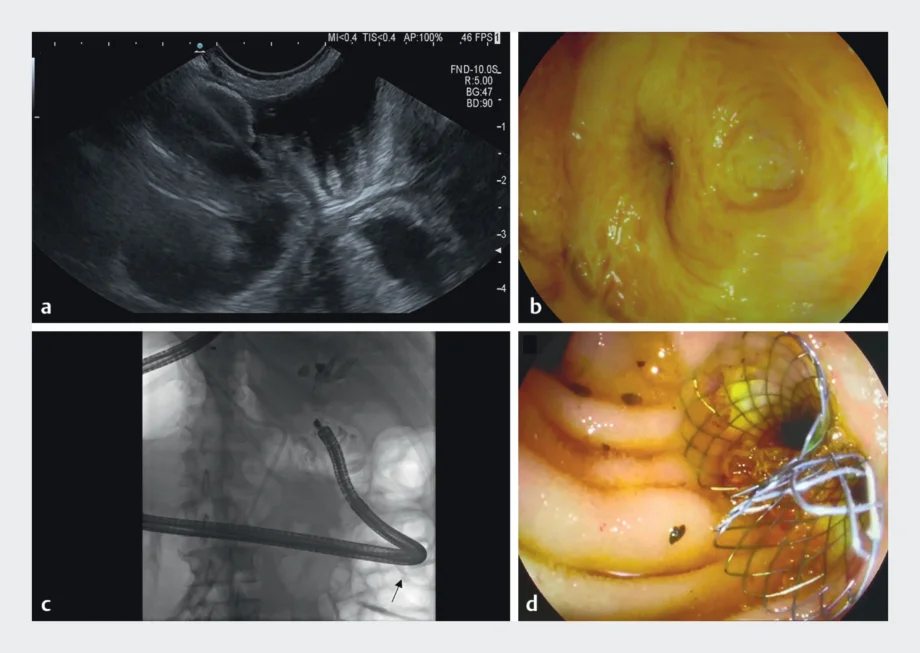

Endoscopic ultrasound-guided short-cut jejunojejunostomy within a long biliary limb post pancreaticoduodenectomy to facilitate endoscopic retrograde cholangiography

Sebastian Zundler, Daniel Klett, Timo Rath, Deike Strobel, Jürgen Siebler, Markus F. Neurath, Maximilian Waldner